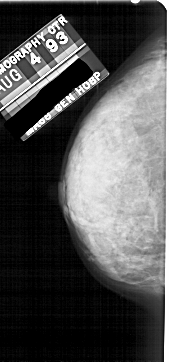

A_1807_1.RIGHT_MLO

RIGHT_MLO LINES 5491 PIXELS_PER_LINE 2461 BITS_PER_PIXEL 12 RESOLUTION 43.5 OVERLAY

FILE: A_1807_1.RIGHT_MLO.OVERLAY

TOTAL_ABNORMALITIES 1

ABNORMALITY 1

LESION_TYPE CALCIFICATION TYPE PLEOMORPHIC DISTRIBUTION CLUSTERED

ASSESSMENT 4

SUBTLETY 2

PATHOLOGY BENIGN